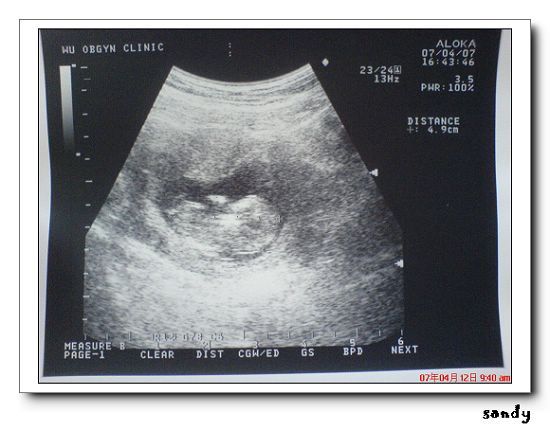

當醫生照到baby的時候

就開始幫我細細的解說 說寶寶的狀況很好 位置也不錯

頭頭的位置 手手的位置 腳腳的位置 目前4.9公分等等

我本來以為醫生沒有把這次的超音波照片給我

後來才發現醫生有給我 真的是超開心的

baby和上次不ㄧ樣喔

他躺的方向換了 這次是頭頭在右邊 小腳腳在左邊

他比上次十週大的時候又多了1.5公分 (這次是十ㄧ週半)

而且頭頭的部份又大了許多喔